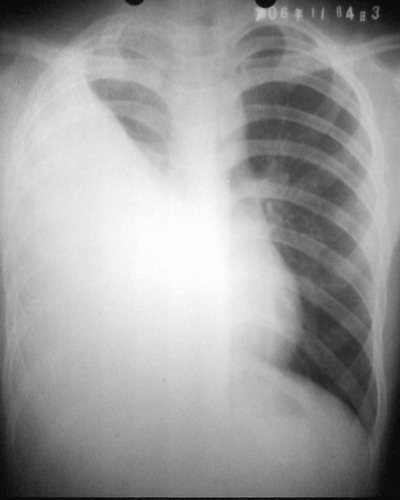

患者/男/17y/因右侧胸痛,发热不退来院拍了个平片!片子质量不好主老师们给个意见吧!谢谢你们!

右侧膈角清晰可见! 左侧肺未见明显异常!请大家给个意见吧!我想给他做个ct! 是不是以先抗炎治一个啊???

右侧胸腔大量积液伴胸膜肥厚,建议ct检查

右胸第1前肋间以下肺野密度均匀一致性增高,内上缘清晰,右隔面/肋隔角消失,其内可见肋骨影,肋间隙无明显改变,胸廓无塌陷,纵隔/气管无移位,考虑右侧大量包裹性积液。

右侧中下野及外带大片状具外内低弧形边缘的致密影,气管,纵隔向左侧偏移,是一个典型的右侧大量胸腔积液!!!应该考虑为结核性的,治疗是先控制症状,然后抽液并服用抗结核药物。

右侧胸腔大量积液伴胸膜肥厚[胸腔积液量大,气管稍左移,心脏无明显移位]。

右大量胸腔积液,这么多胸水,且纵隔及心影移位不明显,为什么没有考虑有肺不张呢,请各战批评指正。

右侧胸腔大量积液伴肺中下叶不张及右肺上叶膨胀不全,性质待查,请结合临床或进一步检查.

纵隔未见明显移位,右侧肺野大片密度增高影,右心缘、右肋膈角及膈面显示不清,考虑胸腔积液伴肺不张情况,建议ct看一下是不是支气管结核。

右侧胸腔积液,包裹形成,伴肺不张,病人年青,考虑结核性胸膜炎可能性大